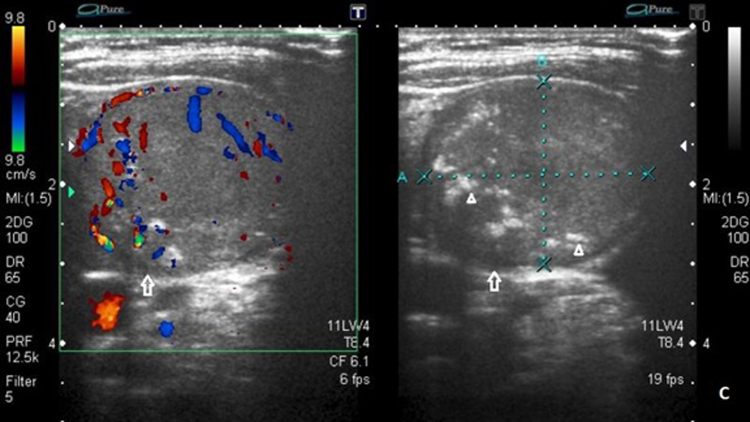

We present a case of a woman treated for breast carcinoma (BCA) found to have a benign hyperfunctioning nodular goiter, its likely transformation to MTC, and its treatment. Family history revealed papillary thyroid cancer in her nephew.